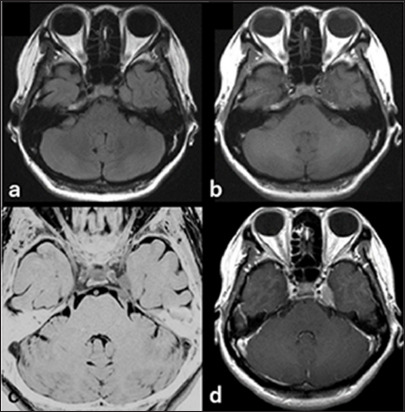

Case description: A case of a 42-year-old woman presented with facial numbness and headache. Magnetic resonance imaging revealed a 25-mm enhancing mass in the left Meckel cave, initially suspected to be a trigeminal schwannoma. Craniotomy and tumor resection were performed. Intraoperative findings and rapid pathology indicated marked inflammatory cell infiltration without features of schwannoma. The final diagnosis was inflammatory pseudotumor, with no evidence of IgG4-related disease or malignancy. Postoperative symptoms improved, and only a short course of steroids was administered.